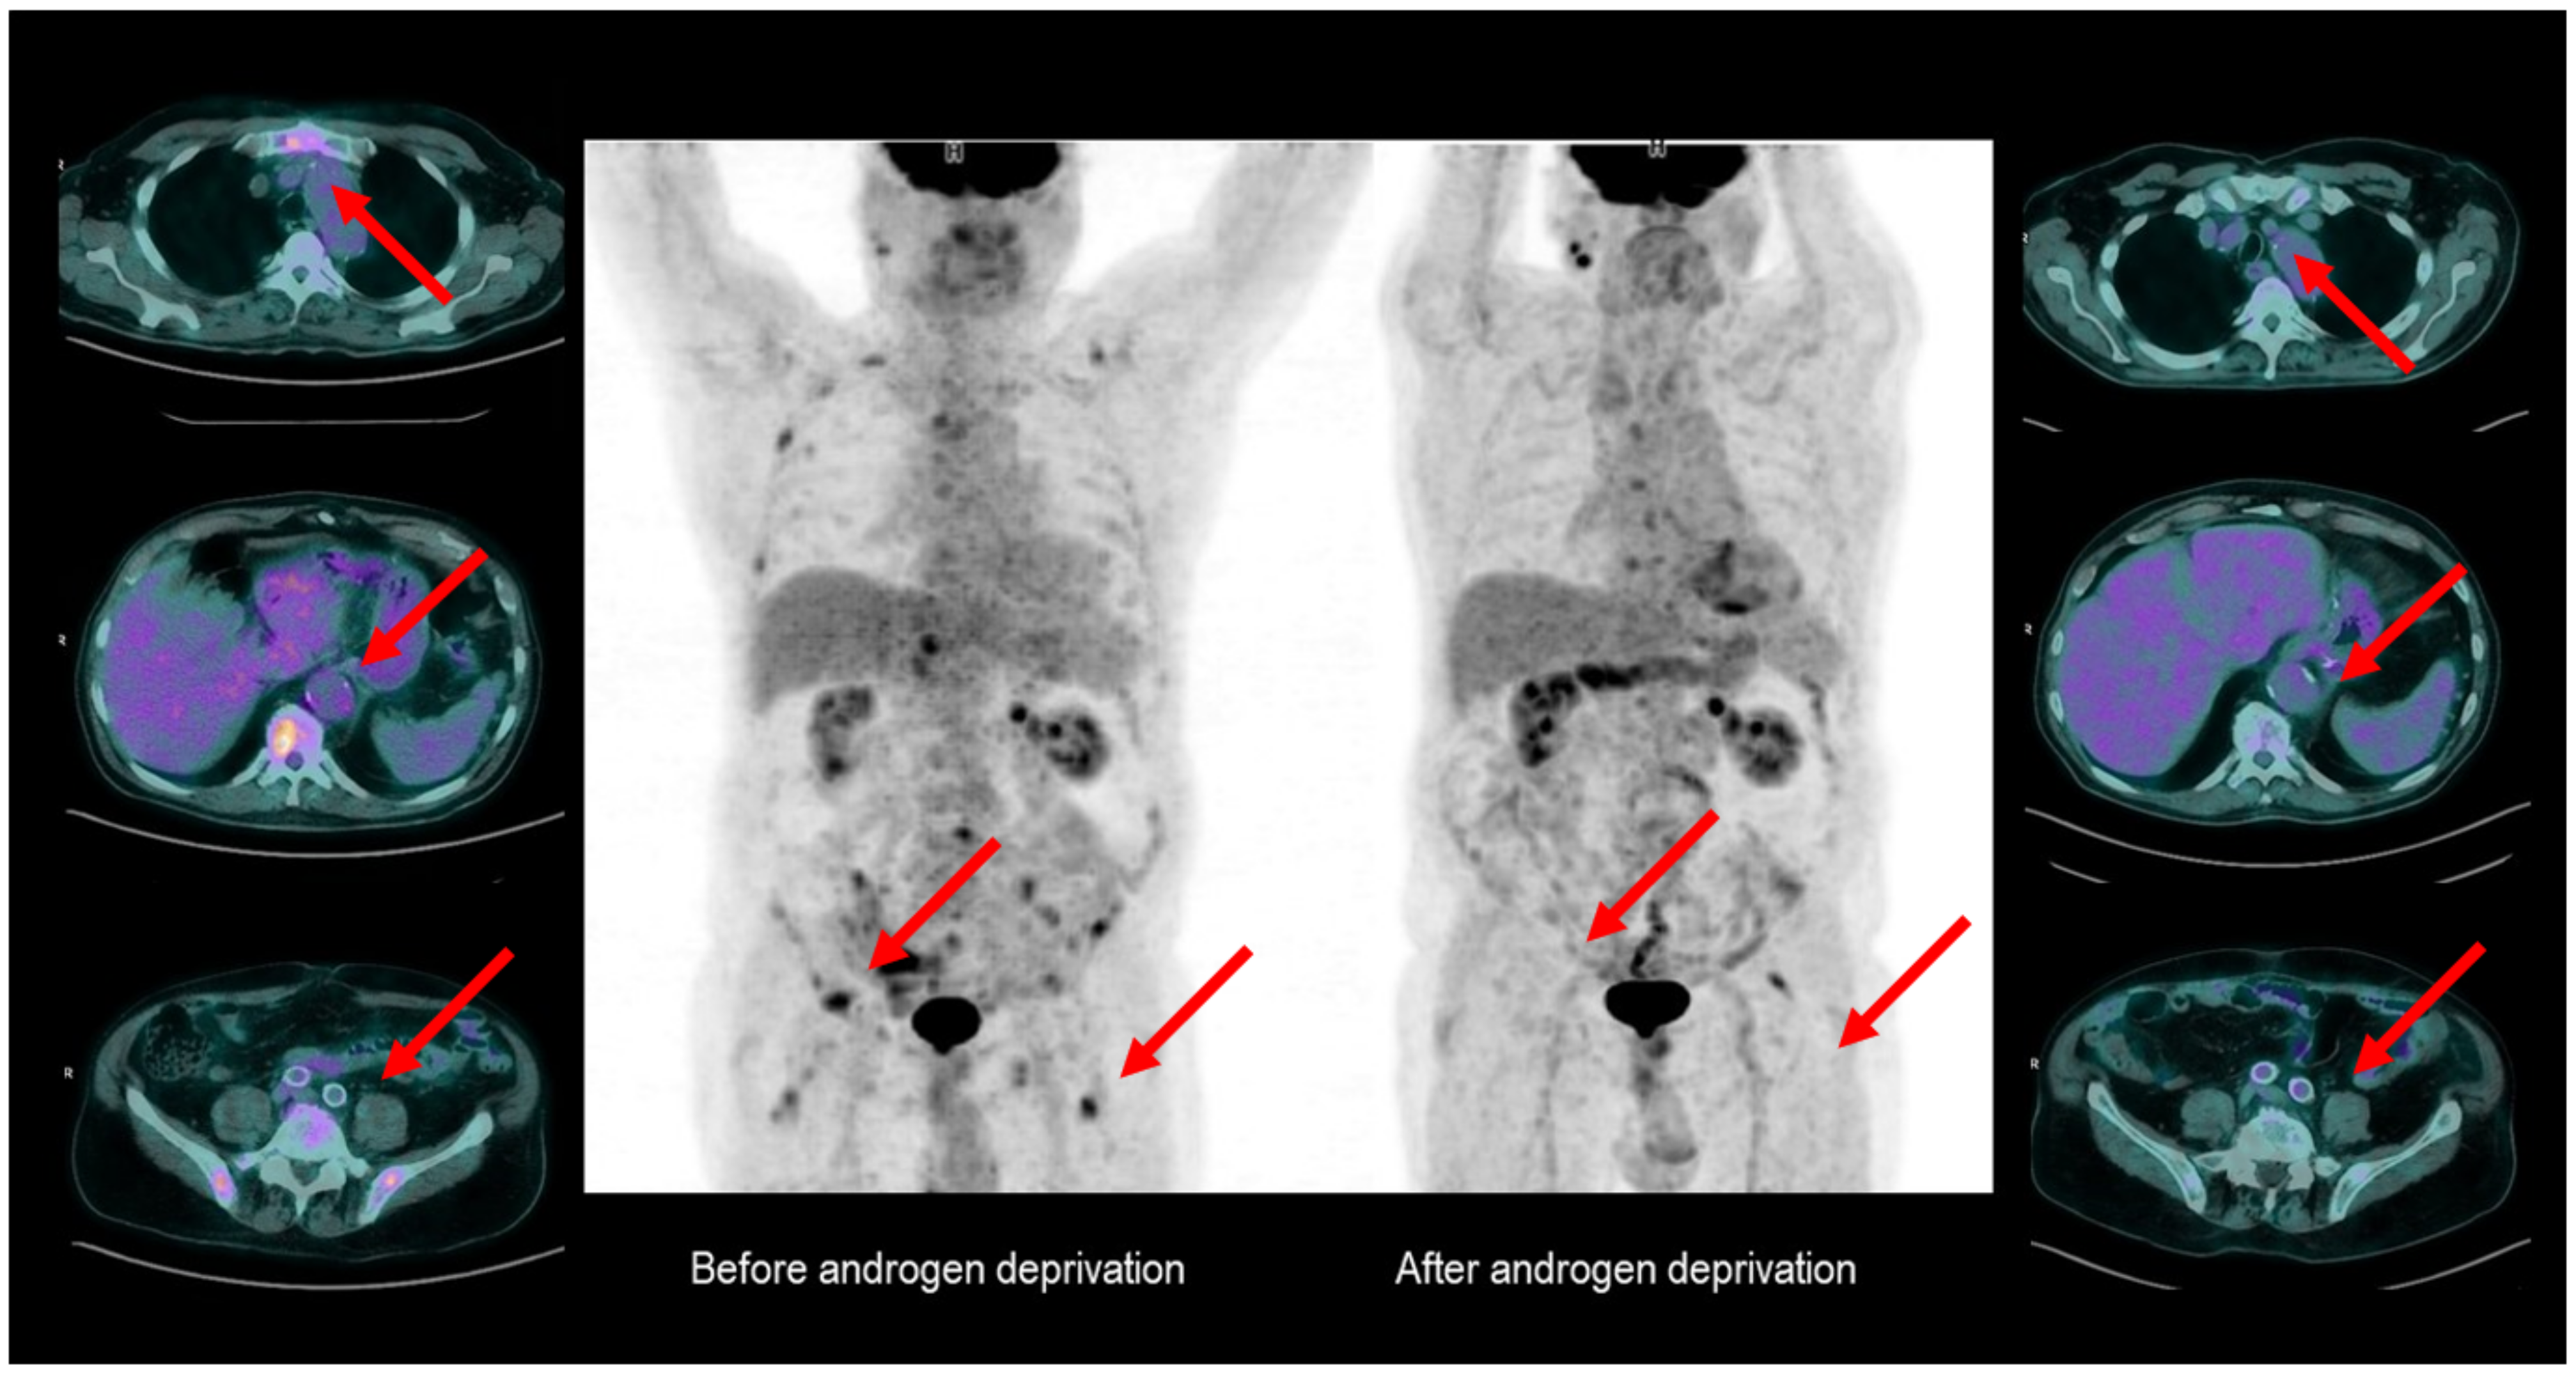

3. FDG PET as a Potential Tool for Therapy Monitoring in Hormone-Sensitive PCa

- Oyama, N.; Akino, H.; Suzuki, Y.; Kanamaru, H.; Ishida, H.; Tanase, K.; Sadato, N.; Yonekura, Y.; Okada, K. FDG PET for evaluating the change of glucose metabolism in prostate cancer after androgen ablation. Nucl. Med. Commun. 2011, 22, 963–969. [Google Scholar] [CrossRef]

- Jadvar, H.; Desai, B.; Quinn, D.; Dorff, T.; Pinski, J.; Conti, P.; Groshen, S. Treatment response assessment of metastatic prostate cancer with FDG PET/CT. J. Nucl. Med. 2011, 52 (Suppl. 1), 1908. [Google Scholar]

- Jadvar, H.; Velez, E.M.; Desai, B.; Ji, L.; Colletti, P.M.; Quinn, D.I. Prediction of Time to Hormonal Treatment Failure in Metastatic Castration-Sensitive Prostate Cancer with 18F-FDG PET/CT. J. Nucl. Med. 2019, 60, 1524–1530. [Google Scholar] [CrossRef] [PubMed]